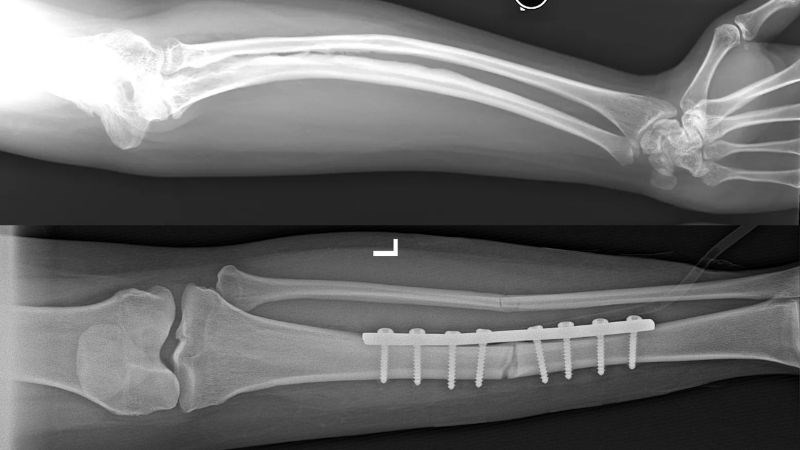

X quang thường là phương pháp chẩn đoán đầu tiên được sử dụng khi có triệu chứng mới xuất hiện. U nang xương phình mạch có một số đặc điểm đặc trưng trên hình ảnh X quang:

Hình ảnh X quang thường không đủ để mô tả u nang xương phình mạch, nên cần phối hợp với chụp cộng hưởng từ để đưa ra chẩn đoán chính xác. MRI giúp xác định tính chất của u nang bằng cách:

Các hình ảnh trên phim X quang hoặc phim MRI không đặc trưng đối với nang xương phình mạch, vì chúng cũng có thể xuất hiện ở các loại u xương khác như u tế bào khổng lồ, nang xương đơn độc hoặc ung thư xương dạng xương.

Đặc biệt, ung thư xương dạng xương có thể gây ra sự phình tĩnh mạch, làm cho việc phân biệt với nang xương phình mạch trên hình ảnh trở nên khó khăn. Vì vậy, việc tiến hành sinh thiết mô u để phân tích là biện pháp chẩn đoán chính xác nhất.